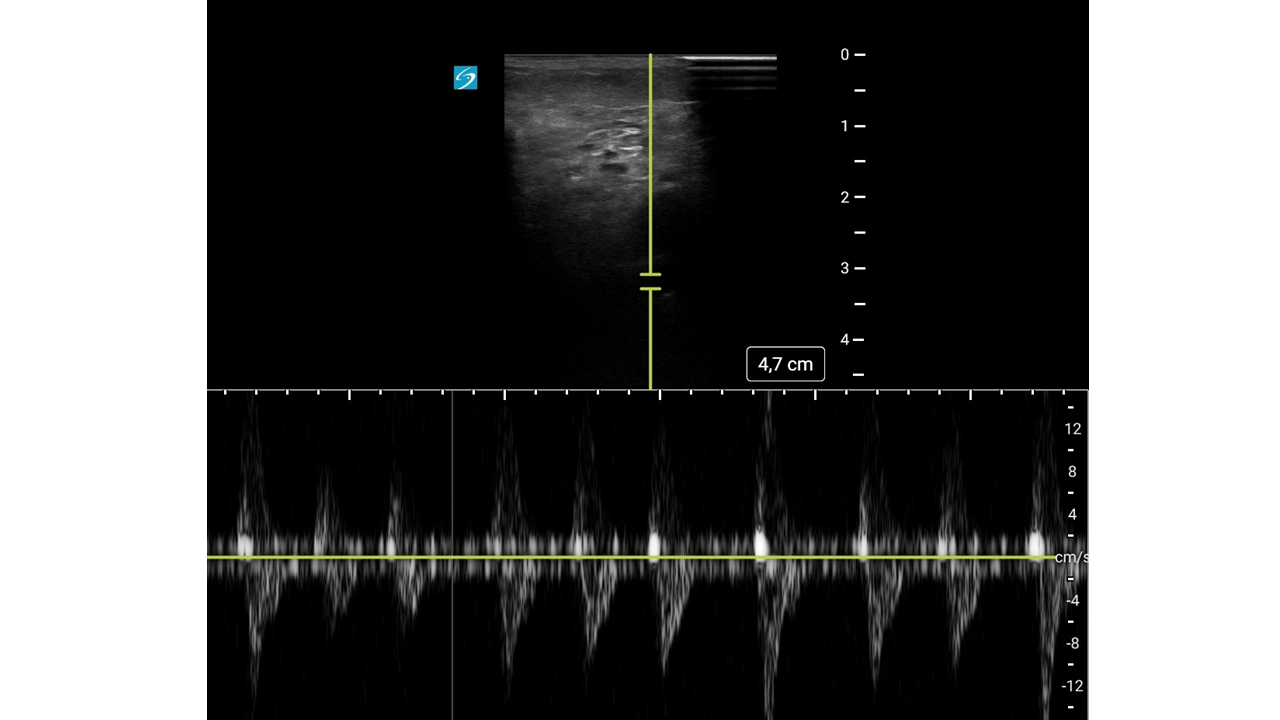

Mujer de 93 años con: fibrilación auricular, enfermedad renal crónica y antecedentes de hemorragias digestivas por las cuales se le había suspendido la anticoagulación oral meses antes.

Motivo de consulta: Dolor súbito, frialdad y pérdida de sensibilidad en la extremidad inferior derecha (EID), con mejoría parcial durante el traslado.

Con mejoría del dolor y pulso poplíteo dudoso, se duda del diagnóstico.

Con sospecha inicial de Isquemia Arterial Aguda (IAA), la mejoría clínica hace dudar abriendo el diagnóstico diferencial a una posible radiculopatía.

Con sospecha clínica de IAA, la ecografía vascular es clave para confirmar el diagnóstico. Su curva de aprendizaje es rápida, se puede utilizar en cualquier punto del sistema y permite derivar al paciente a un centro útil evitando demoras potencialmente fatales.